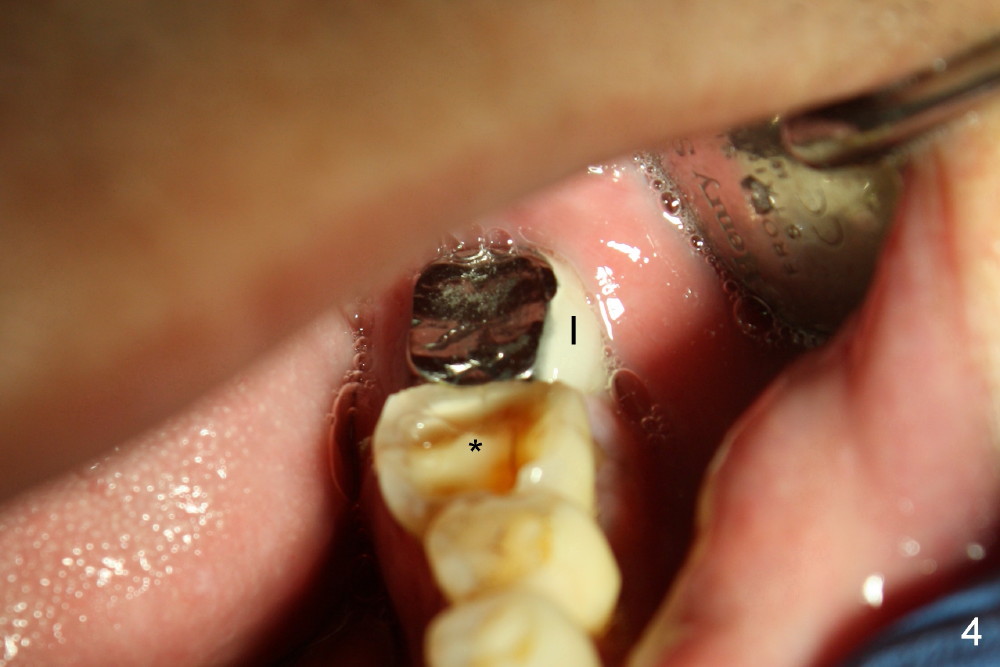

病人回来时说已经不太痛了,但是颊侧近中根尖仍有轻度肿胀,触痛(图三箭头),反复告诉他不处理不行,他强调采纳最保守治疗,不愿拔牙植牙,左下第二磨牙植牙(图四I)不好用,好像与真牙不一样。其实他牙齿磨耗尤其严重(图一至图四显示四个象限后牙,*代表第一磨牙),两个磨牙牙冠一定要有金属合面,否则陶瓷会断裂,而且牙冠容易脱落。左下第二磨牙植牙折腾部分原因是对合牙(左上第二磨牙)往下掉(supraerupted,图二S),没有空间放植牙,基牙和牙冠。